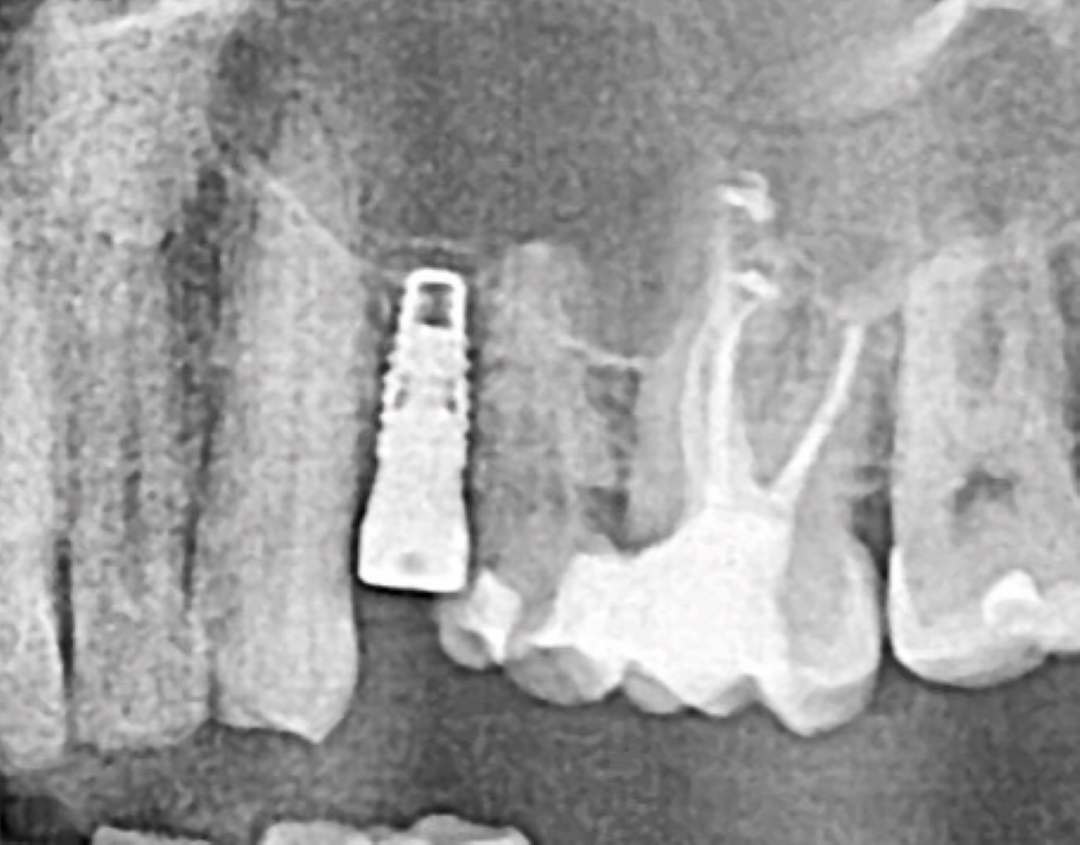

Ранее удаленный зуб 36 - незначительная атрофия по костным тканям и довольно выраженная атрофия по мягким тканям.

Имплант Straumann BLT 4.1*8mm SLActive - установлен в субкрестальное положение, произведено профилирование кортикальной кости системой Straumann Bone Profiler с целью создания более выгодного профиля прорезывания и исключения костной резорбции в области шейки импланта.

Чтобы компенсировать недостаточный объем мягких тканей проведена - мягкотканая пластика деэпителизированным соединительнотканным трансплантантом с неба.

Установлен заживляющий абатмент диаметром 6.5 мм.

Обратите внимание на объем и качество мягких тканей в области будущей финальной реставрации!

Финальная реставрация и диоксид циркония в полную анатомию методом раскрашивания.

Резюме:

Этот кейс мы с Сергеем смело относим к разряду простых - но, если посмотреть на него внимательно - здесь на каждом этапе есть определенные нюансы начиная от разреза и заканчивая финальной реставрацией.

Дьявол кроется в деталях.